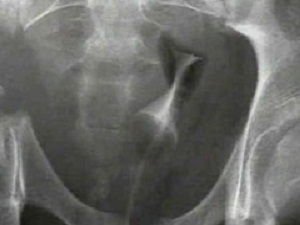

Bu kemiğin kırılması öldürebilir